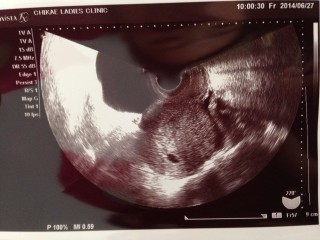

深夜鮮血での出血があり、流産だ…!と青ざめました。 しかし今日病院へ駆けつけたところ、胎嚢はちゃんとあり、 4wのころよりかなり成長していました。 とりあえず一安心です。 1週間自宅で安静に過ごします。

エコー写真

あなたのエコー写真と比べてみては...